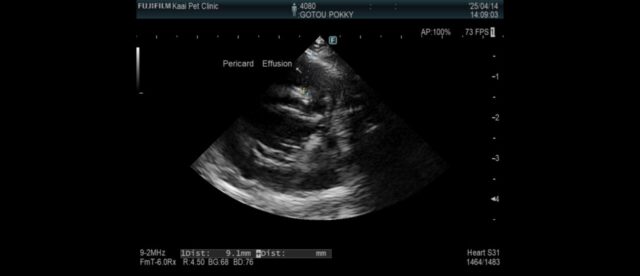

この日、心臓肥大の原因を特定するためのエコー検査を行っていただきました。

心臓に水(心嚢水)が溜まり、加えて肺にも水(胸水)が溜まっているため呼吸が苦しい状態であるとの説明を受けました

心嚢水は抜くことで呼吸が楽になるので、犬だと手術も行えるそうですが、うさぎの心嚢水が溜まるのは珍しいケースな上、オペのリスクが高く、外科的な処置はできないためICUで酸素吸入してから内科療法をメインに治療をすすめるという説明をうけました。